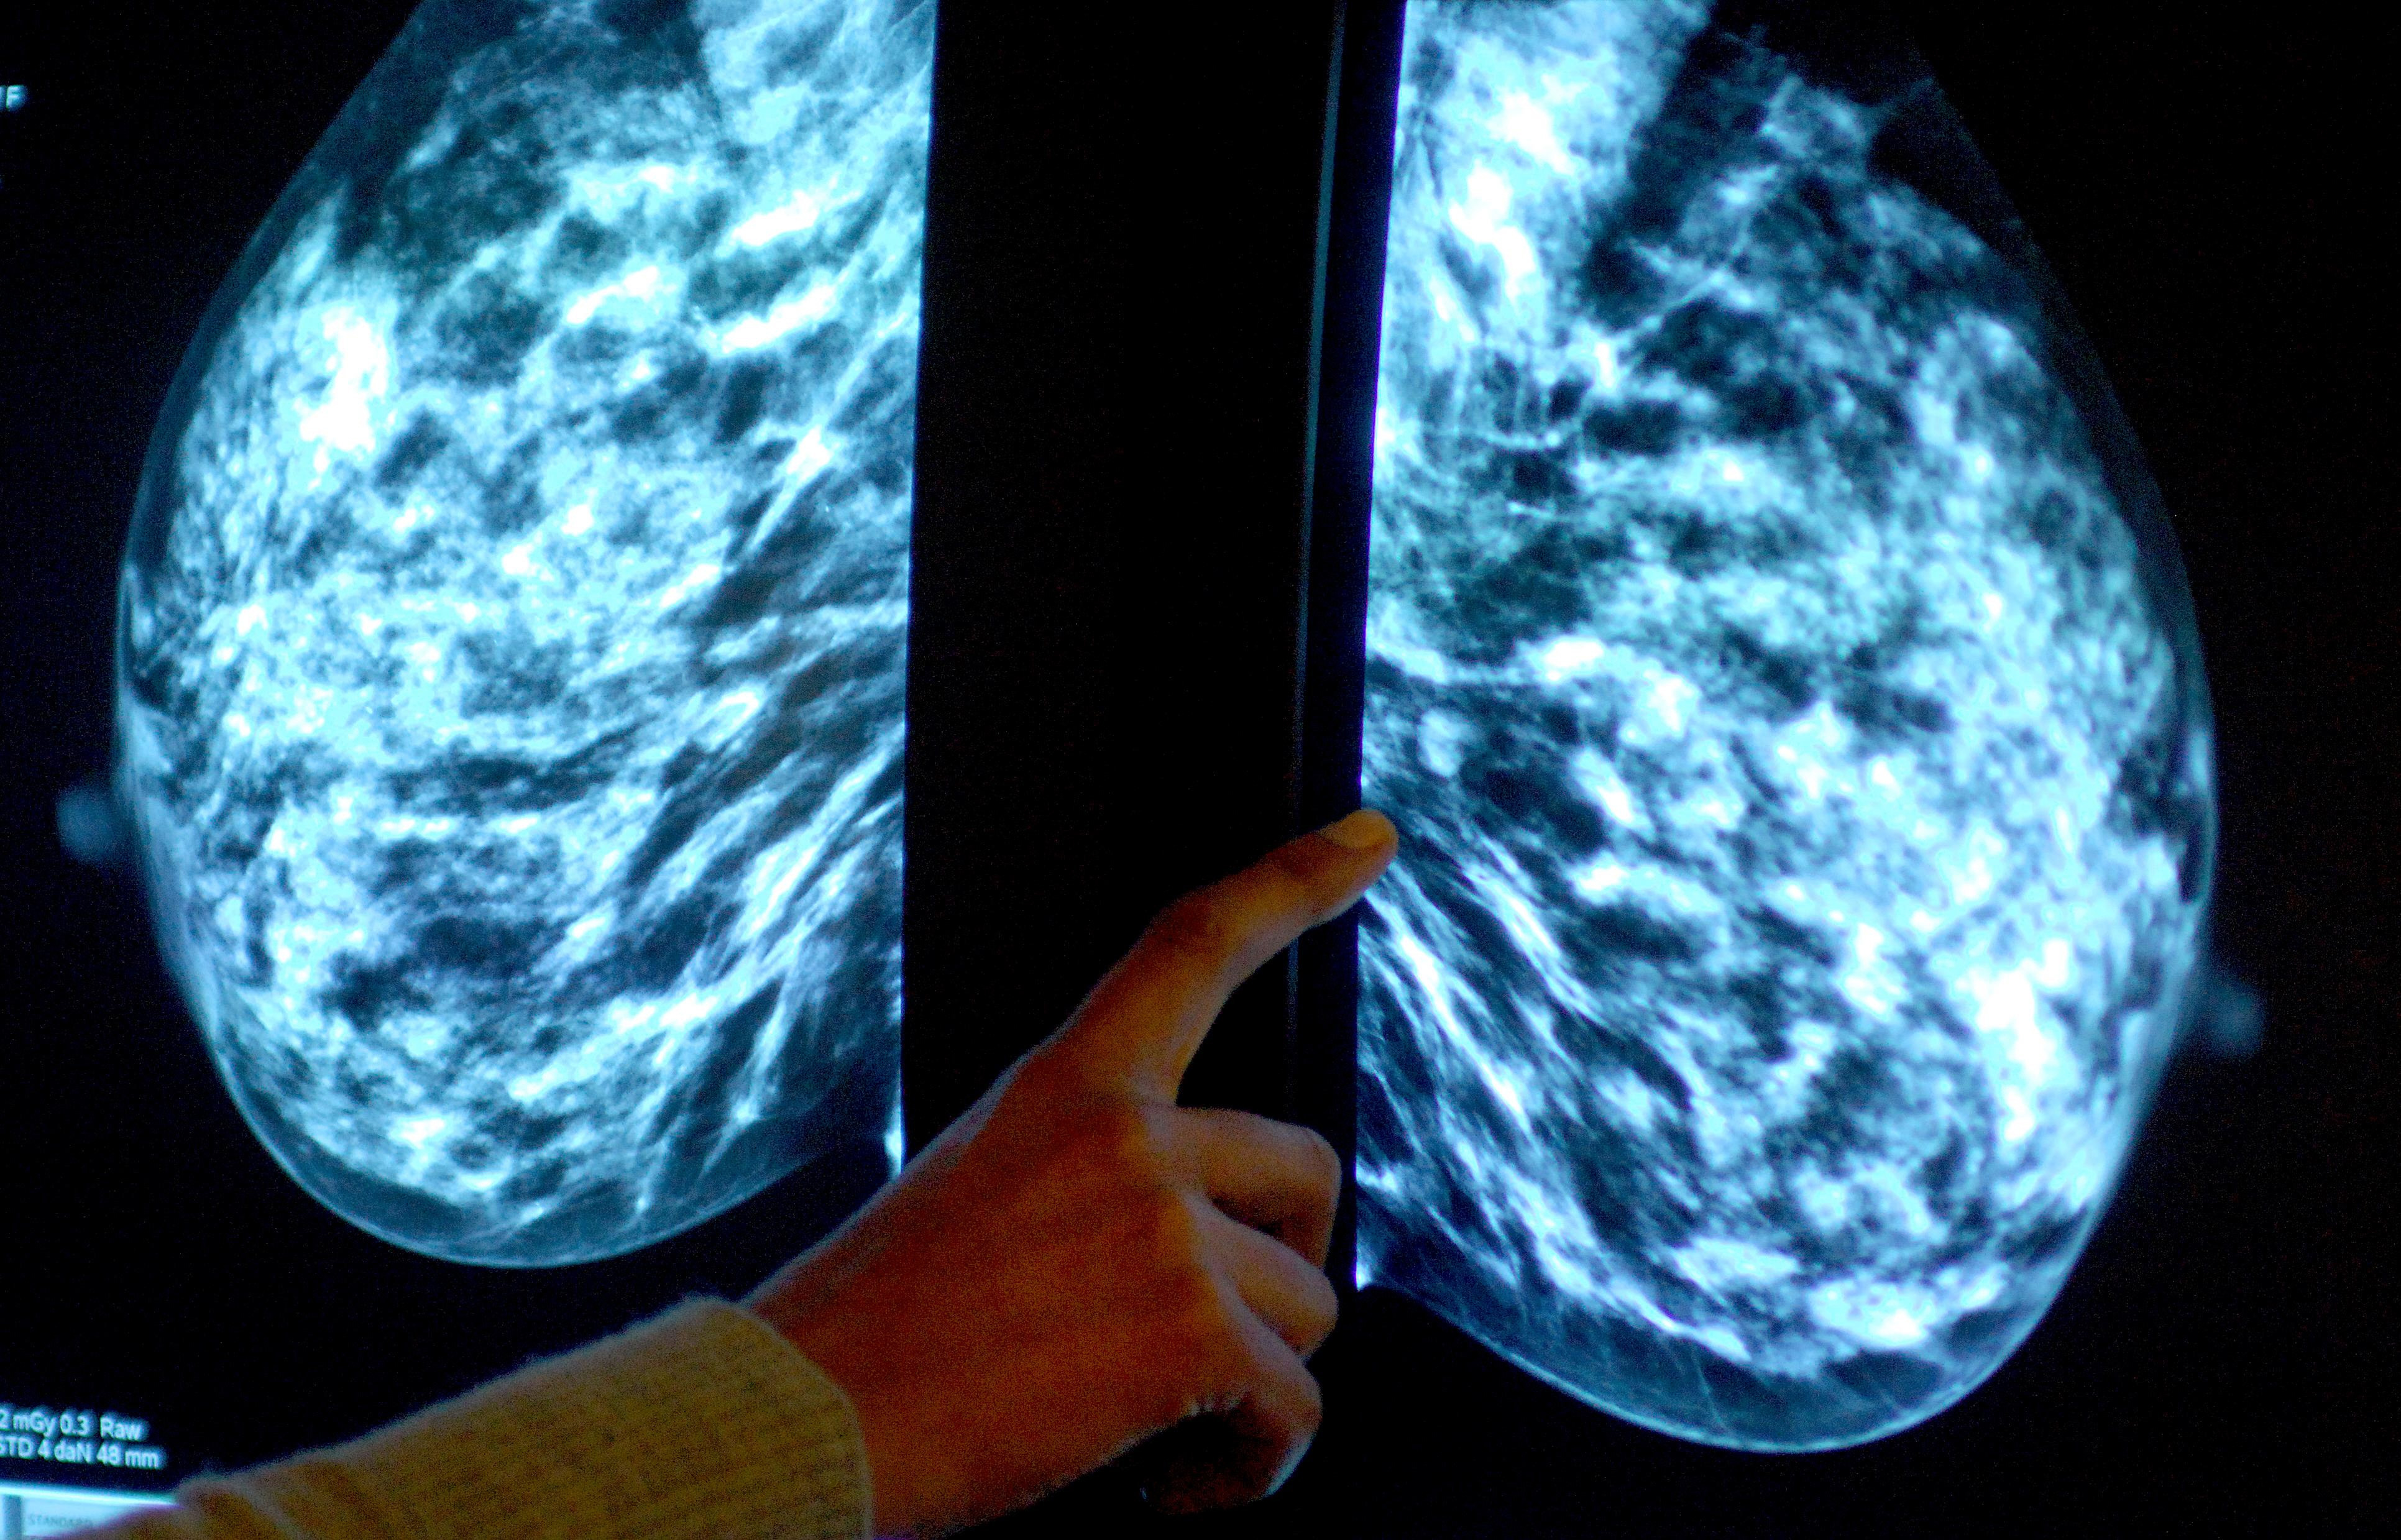

Breast screening uptake in Devon remains below pre-pandemic levels, new figures show.

It comes as charities have said women still face too many barriers to regular testing, as fewer people in England underwent tests than before the coronavirus pandemic

Dr Claire Knight, senior health information manager at Cancer Research UK, said: "Breast screening is an important tool for spotting the early signs of breast cancer at a stage when treatment is more likely to be successful.

"The current evidence suggests that breast screening reduces the number of deaths from breast cancer by about 1,300 a year in the UK."